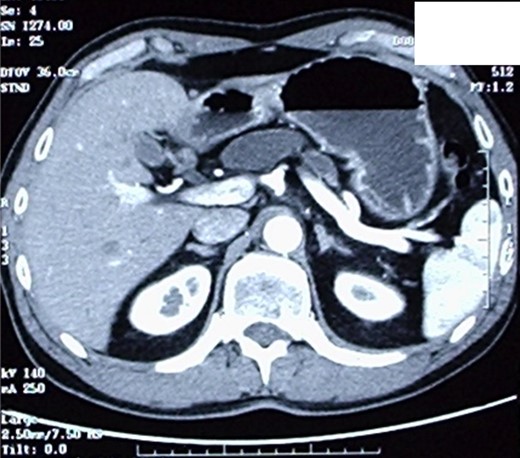

The patient therefore underwent a computed tomography (CT) scan (Figs 1 and 2) that revealed ‘a thickened duodenal wall and a sero-cystic lesion of the pancreatic head without contrast-enhancement, which compressed the duodenal lumen and caused a dilation of the Wirsung duct’. The liver, the gallbladder and the extrahepatic biliary tree were normal. No lymphadenopathy was found.

CT-scan, showing a sero-cystic lesion of the pancreatic head without contrast-enhancement, compressing the duodenal lumen and causing a dilation of the Wirsung duct.

Another image of the CT scan, showing a sero-cystic lesion of the pancreatic head.